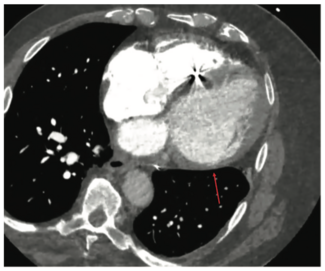

Ablation of ventricular tachycardia in patients with nonischemic cardiomyopathy can be challenging, but several tools are available to improve the success rate and safety of the procedure.